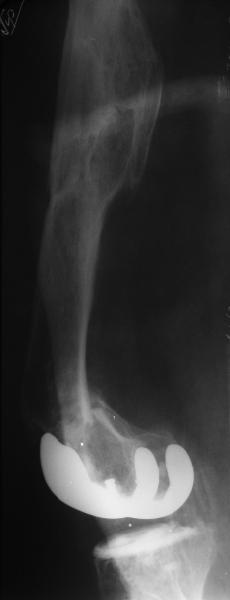

Глубокоуважаемые коллеги, Мужчина 41 года поступил с повторным (предыдущий в 2001 г.) переломом (3-недельной давности) над протезом коленного сустава.

В 1994 множественная травма, в том числе открытый перелом надколенника, осложнившийся гнойным артритом, и на этой же стороне перелом диафиза бедра (лечили в аппарате). В 1998 г. выполнено эндопротезирование коленного сустава.Предыдущий перелом (3 года назад) лечили консервативно, сросся при неустраненном смещении дистального блока бедра кзади ~ на 1 см.Амплитуда движений в коленном суставе перед последним переломом была ~90 градусов. Ходил без дополнительной опоры.Снимки в приложении. Какие будут предложения по поводу оперативного лечения в нынешней ситуации? У нас споры между ретро- и антеградным закрытым интрамедуллярным остеосинтезом.

A male 41 years old transferred to our unit with 3 week old femoral fracture near the knee prosthesis after a mimimal fall. In 1994 he sustained multiple injury with open patella fracture (complicated with septic arthritis), and ipsilateral femoral shaft fracture treated by ex-fix. TKA performed in 1998. In 2001 he got a periprosthetic fracture which was treated nonoperatively and healed with ~1 cm dorsal displacement of the distal femoral block. Knee ROM prior the recent injury was about 90-95 degrees. He didn't use walking aid.Images attached. I request your suggestions regarding surgical options in the situation? We mostly discuss ante- vs retrograde closed nailing.

I think retrograde nails through total knees give good distal fixation. I'm not sure what kind of TK prosthesis but nearly all of the designs in the US have a big enough space to accept a 10 mm retrograde nail between the condlyles of the total knee.

My concern in this case would be the deformity of the old fractures might not allow for a straight nail but might be more amenable to a locking plate; or particularly in Russia, XF.